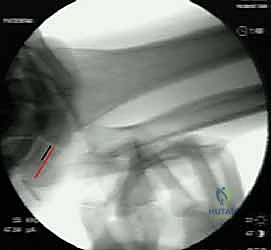

Image

FIG 3 • The still photographs shown have been captured from a fluoroscopy video of a wrist with ulnocarpal instability during the supination test. A. Top of the examination cycle with the wrist in neutral position. B. Bottom of the examination cycle. In both images, the black line represents the distance between proximal edges of pisiform and triquetrum. The red line indicates the length of the triquetrum. The shorter length of the red and black lines in B compared with A demonstrates the ulnocarpal instability present during dynamic testing.